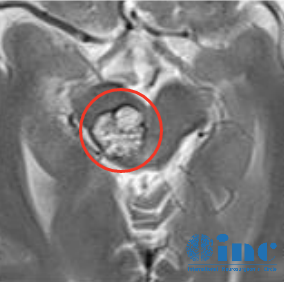

患者為40多歲的秦先生,18年3月查出腦干中腦海綿狀血管瘤,頭暈癥狀3天后恢復(fù)正常。20年3月,一開始發(fā)現(xiàn)海綿狀血管瘤出血,并感覺左手及左側(cè)面部麻木,3-4個(gè)月后好轉(zhuǎn),這期間未做任何治療。保守治療效果不佳,21年8月,發(fā)生二次出血,麻木比一開始加重,并增加左腳麻木及酸軟無(wú)力,走路腳脹痛,感覺像中風(fēng)一樣。為了確定是否是腦干海綿狀血管瘤,秦先生做了8次腦部核磁檢查。

說(shuō)到腦干海綿狀血管瘤,我發(fā)現(xiàn)很多人都有個(gè)誤區(qū),他們會(huì)擔(dān)心這是不是惡性腫瘤。首先我們要明確,雖然它的名字里帶了個(gè)瘤字,但其實(shí)海綿狀血管瘤是一種血管畸形病變,并不是腫瘤,身體上也是會(huì)長(zhǎng)的,只是我們說(shuō)的這種病變是長(zhǎng)在腦干,形狀就像桑葚、爆米花一樣。